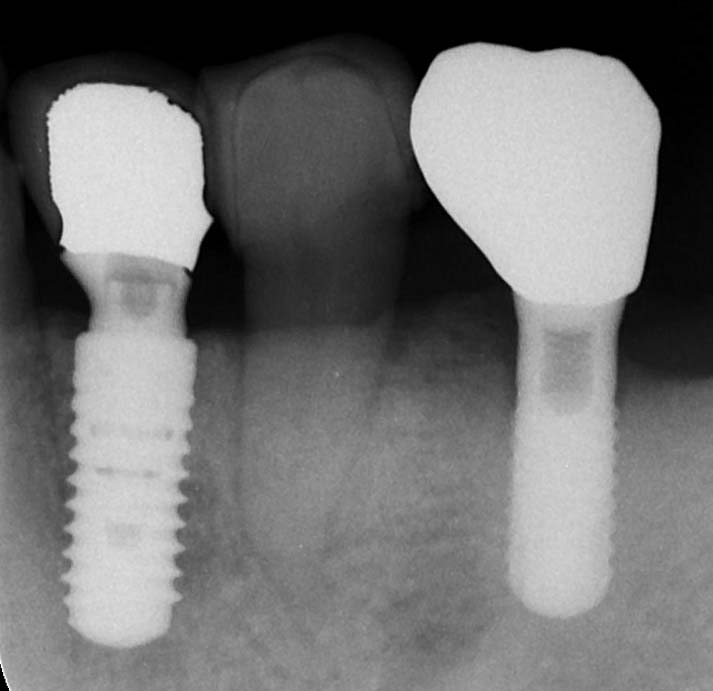

左下奥歯の歯周組織再生療法後2年の患者さんがメンテナンスで来院されました。インプラントに挟まれた天然歯の周囲骨が再生し、術前に存在していた動揺も収まりました。レントゲン上でも改善が認められました。露出させた歯根面にエムドゲインという薬を塗布し、骨欠損のスペースに骨補填材と言われえる材料を填入して歯肉を縫合しました。骨欠損の深さがあっても幅が狭いケースは再生療法をやる上では好条件という10年近く前に受講したEPIC(evidence based periodontology and implantology course、二階堂正彦先生主催、清水宏康先生インストラクター)というセミナーで勉強させていただいた通りでした。やはり単根歯(根っこの数が一つで前歯や一部の小臼歯、根っこの数が二つ以上は複根歯と呼ばれ、奥歯や一部の小臼歯がそれにあたる)の再生療法は行いやすいため比較的成績が良いようです。このケースは手前のインプラント埋入と同時に行った下顎小臼歯の再生療法でした。小臼歯周囲骨欠損の手前が天然歯やインプラント上部構造がなかったため(視野を遮るものがなかったため)、さらに手術がやりやすかったと言えます。根分岐部病変と呼ばれる複根歯の又の部分にできる骨欠損の再生は未だに確実性に劣ると言われています。解剖学上複雑な形態をしていると見えずらいし、見えなければ廓清も困難になることを意味します。廓清が不十分であれば(きれいにできなければ)骨再生も十分期待できない事になります。今後、手技や材料の開発が進んでこれらへの対応レベルが向上し成績が上がることが望まれます。歯周病も数十年前は「それ以上悪くならないように」という概念のもとで治療が行われていたことが一般的だったことを考えると、再生療法は革命と言えると思います。ただ何でも治るわけではなく適応症が限られることと、インプラント埋入なんかよりはるかに繊細な技術が要求されることが問題とも言えます。今週末には二階堂先生が主催されている水道橋歯周病勉強会の月一回行われている定例会があり、イタリアの有名な歯周病科医であるコルトレーニ先生の論文を抄読します。この機会に今までの知識、情報の整理ができればと考えています。再生療法を望まれる患者さんも増える傾向にあり、適応症の判別、技術の向上、使用材料の選別等、常に新しい信頼性のある情報を得ながら、より良い結果が出せるように気を引き締めたいと思います。